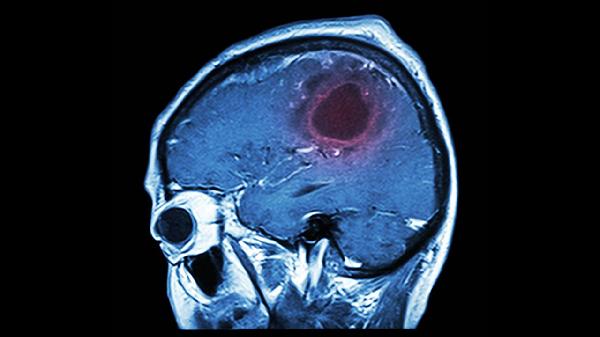

脑血栓片主要用于治疗缺血性脑血管疾病,如脑血栓形成、脑栓塞、短暂性脑缺血发作等。脑血栓片能改善脑部血液循环,帮助恢复脑功能,缓解脑血管疾病引起的一系列症状。